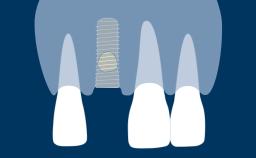

Radiography plays an important role in implant dentistry.

These investigations are used to assist in the diagnosis of pathology, aid in implant treatment planning, and monitor peri-implant bone levels on maintenance assessments, such as this image taken at a 1-year follow-up visit.

To achieve these goals, radiographic images need to meet basic standards of quality.

They need to have sufficient density and contrast to clearly show changes and to demonstrate sharp detail. Distortion, blurring from movement, and other artifacts limit a radiograph's diagnostic value.